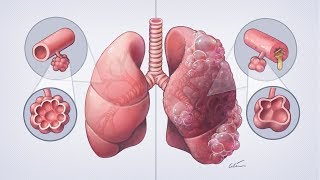

Painting a medical illustration for TV: Healthy vs COPD lungs video

Painting a medical illustration for TV: Healthy vs COPD lungs

Painting a medical illustration for TV: Healthy vs COPD lungs COPD Exacerbations Expressed - Painting a Picture of a COPD Flare-up

Painting a medical illustration for TV: Healthy vs COPD lungs

Painting a medical illustration for TV: Healthy vs COPD lungs COPD Exacerbations Expressed - Painting a Picture of a COPD Flare-up